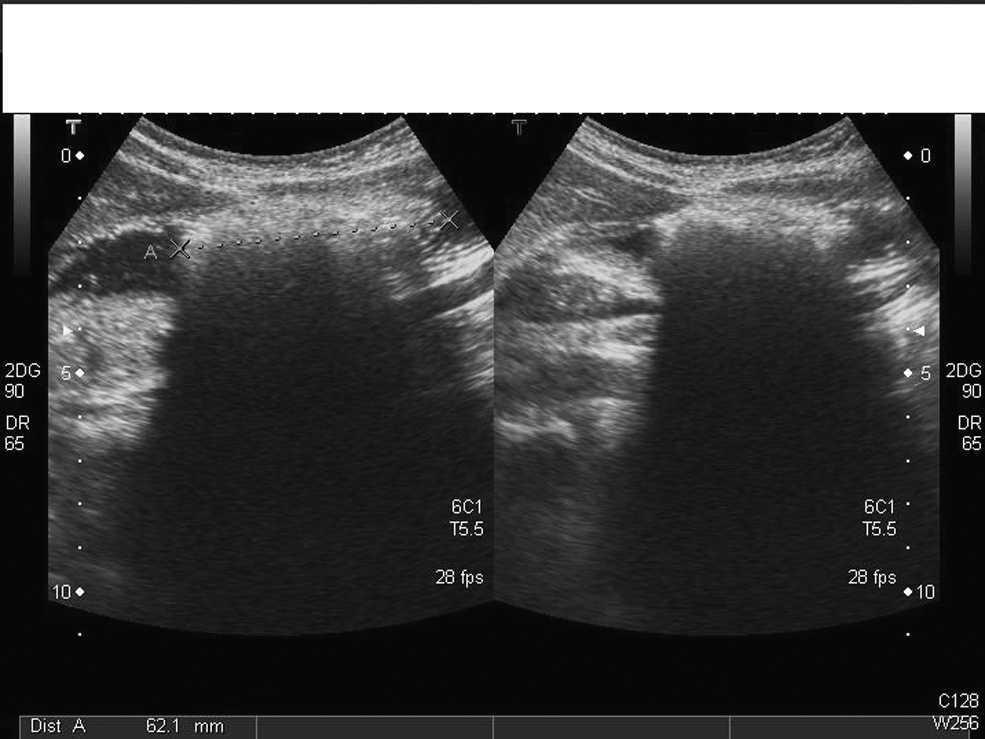

Se inicia tratamiento sintomático. Ante la persistencia de los vómitos, se realiza radiografía abdominal, en la que se visualiza el estómago con contenido y distribución normal de gas intestinal. En la ecografía abdominal se visualiza (fig. 1) el estómago distendido, con una imagen hiperecogénica de 6 cm de longitud en el antro, ovalada y que impide el vaciamiento gástrico (posible cuerpo extraño). Se realiza una interconsulta a cirugía y la paciente ingresa. Durante el ingreso se realiza tránsito digestivo (fig. 2) que confirma la presencia de una masa densa en el estómago que ocupa toda la cavidad gástrica y deja pasar contraste. Se interviene quirúrgicamente a la paciente para la extracción del tricobezoar mediante gastrostomía. Durante el ingreso inició una evaluación psicológica.

Figura 2. Tránsito digestivo superior: pone de manifiesto masa densa heterogénea en estómago que ocupa toda la cavidad gástrica.

Los síntomas del tricobezoar son dolor abdominal, náuseas, vómitos, anorexia, saciedad temprana, debilidad, pérdida de peso y masa abdominal. Sin diagnóstico puede dar lugar a complicaciones serias: obstrucción intestinal, perforación, pancreatitis, invaginación, hemorragia intestinal por gastritis, ictericia obstructiva, enteropatía pierdeproteínas y anemia. Puede haber alteración del patrón de deposiciones1,3,4. A menudo pasa desapercibido porque no se menciona la historia de tricofagia. El diagnóstico se basa en la clínica y en las pruebas de imagen. La radiografía abdominal no es diagnóstica (masa heterogénea en el estómago que puede confundirse con un estómago lleno de comida), y se debe confirmar con tránsito digestivo (el contraste identifica una masa intraluminal y libre). La ecografía (imagen hiperecogénica con sombra acústica) y la tomografía computarizada (la imagen más característica es una masa intraluminal heterogénea con patrón de aire moteado, y es más sensible para definir la localización) son las pruebas más fiables5–7. Mediante la laparoscopia se visualiza y ésta puede ser eficaz en la extracción, pero a menudo requiere laparoscopia o laparotomía2,3,8. Se recomienda tratamiento psiquiátrico para prevenir recidivas.